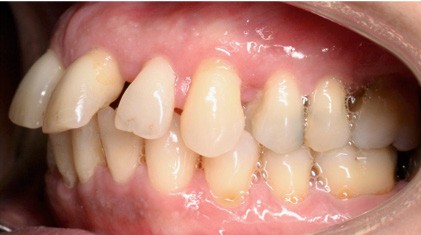

À l’examen endo-buccal (fig. 2), on note une formule dentaire complète (absence des 8) avec présence de restaurations multiples étanches, un bon contrôle de plaque et une parodontite de stade 4 grade C stabilisée [3], des récessions gingivales et des mobilités dentaires généralisées (degré 2, classification de Miller). L’arcade mandibulaire présente une courbe de spee importante avec égression du bloc incisivo-canin. Les milieux inter-incisifs sont alignés, le recouvrement est normal, le surplomb est augmenté à 3 mm et associé à des diastèmes et de la vestibulo-version des incisives maxillaires. Les relations antéro-postérieures canine et molaire sont en Classe I d’Angle.